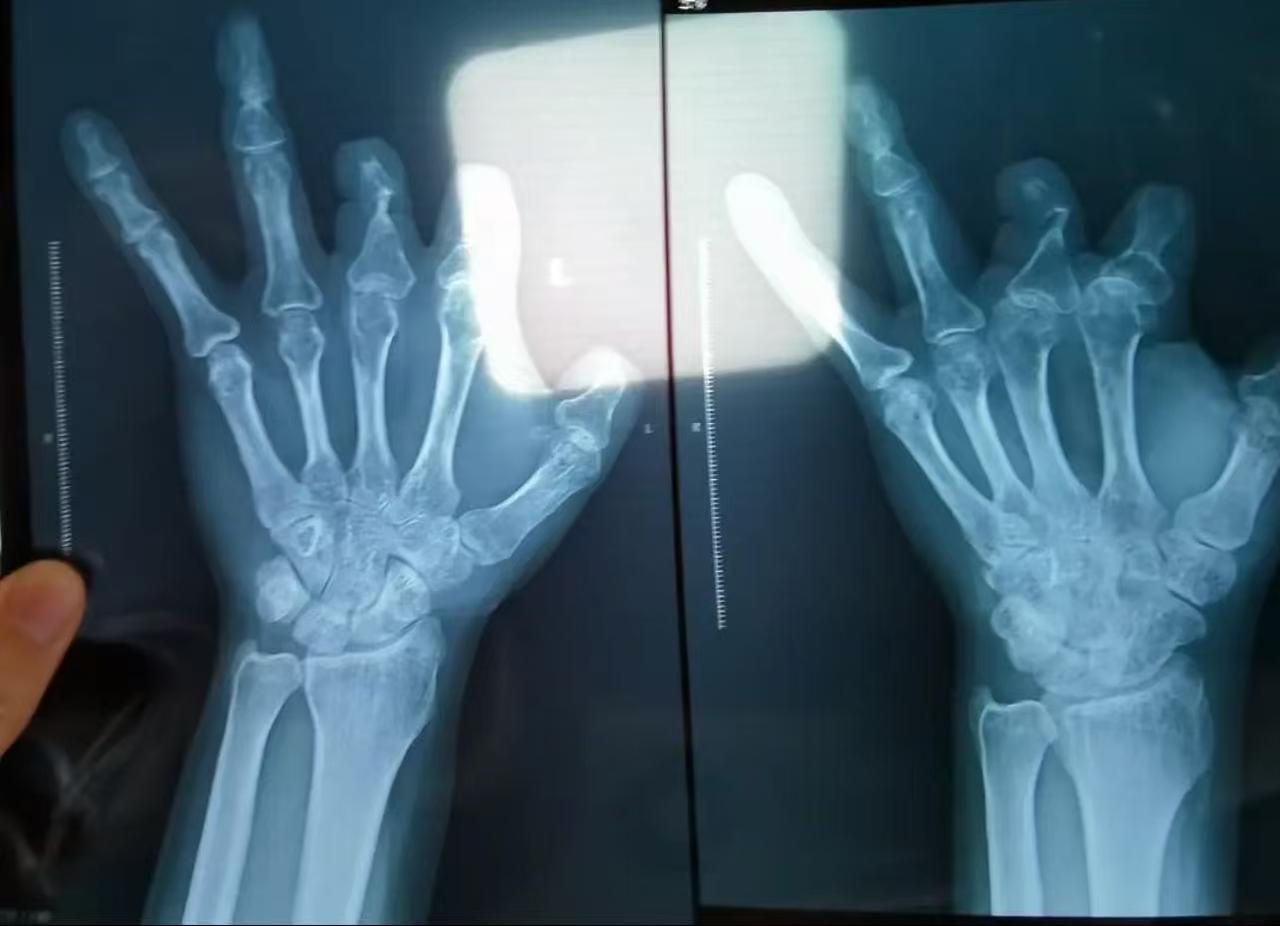

这事儿听得我后脊背发凉,医生为了拿20%的回扣,骗病人花10万块钱买昂贵的吻合器,结果吻合器压根没使用,转手就被医生扔进了垃圾桶!而警方深入调查,更是大吃一惊,被坑的不是一个人,而是整整94人!网友:简直刷新了做人的底线。 事情要从河南中牟的彭先生说起。他在一次意外中左手四根手指被切断,血流如注,紧急送进郑州大学第一附属医院。 手术由急诊外科副主任医师王福建主刀,整整12个小时,显微镜下缝合神经、血管、肌腱…… 而账单却让人心惊:仅一项叫“微血管吻合装置”的材料,就花了10.08万元! 单价1.68万,用了6个。医生解释说:“这是进口高端器械,能提高断指成活率,必须用。” 可术后恢复极差,手指还是坏死了。彭先生心生疑虑,在律师建议下拍了X光片——结果令人毛骨悚然:那6个本该留在体内的吻合器,一个都没影儿! 要知道,这种装置含有不锈钢针,X光下清晰可见,绝不可能“被吸收”或“消失”。唯一的解释是:压根没放进身体里。 更令人发指的是,这并非孤例。 2018年,木工王海森在工地被电锯削掉拇指,也被送到郑大一附院。手术后欠费3万,其中2个吻合器就花了3.36万。一年后,有人悄悄告诉他:“那玩意儿根本没用。”他不信,直到2021年拍X光片——果然,空空如也。 警方顺藤摸瓜,揭开了一张持续4年的黑网: 从2016到2020年,王福建与器械代理商勾结,约定每卖一个吻合器,拿20%回扣。他明知某些患者根本不适用(比如血管太细、损伤太重),却照常计费,甚至把器械缝在血管旁边的肌肉里“做样子”,只为骗过术后X光检查。 94名患者,上至干苦力的农民工,下至刚满1岁的幼儿,全成了他敛财的工具。 总计虚收费用超205万元,个人受贿105万。而那些被“省下”的吻合器,有的被扔进医疗垃圾桶,有的被重复“展示”给下一个病人看——一条人命的希望,成了他抽屉里的提成单。 直到2021年媒体曝光,他才被停职。但没过多久,医院竟打算恢复其执业资格!王福建干脆申请提前退休,以为能金蝉脱壳。结果2023年底,法网收拢,他被刑事拘留;2025年,法院终审判处12年有期徒刑,罚金40万,违法所得全部追缴。 可12年,能换回94个家庭被欺骗的信任吗?能弥补那个1岁孩子本可能保住的手指吗? 能抚平农民工王海森因多花3万而被迫停工半年的绝望吗? 当救死扶伤的手术台变成回扣交易的柜台,当患者的信任被明码标价,这已不是个别医生的堕落,而是整个监管体系的溃烂。 医院事后整改、追缴赃款固然必要,但若没有透明的手术耗材实时公示、没有第三方独立核查、没有对“高值耗材滥用”的自动预警,今天倒下一个王福建,明天还会有李福建、张福建。 王福建被判了12年真的不冤,这种人就不配穿那身白大褂。 以后进医院,咱们还得长八个心眼,防病还得防人心。 我们总说“医者仁心”,可当利益链条足够粗,仁心就会被碾成粉末。 别再只靠患者自己拍X光片来维权——那不该是救命的最后防线,而应是监管的日常起点。 否则,每一次躺上手术台,都像在赌命:赌医生是天使,还是穿着白衣的商人。